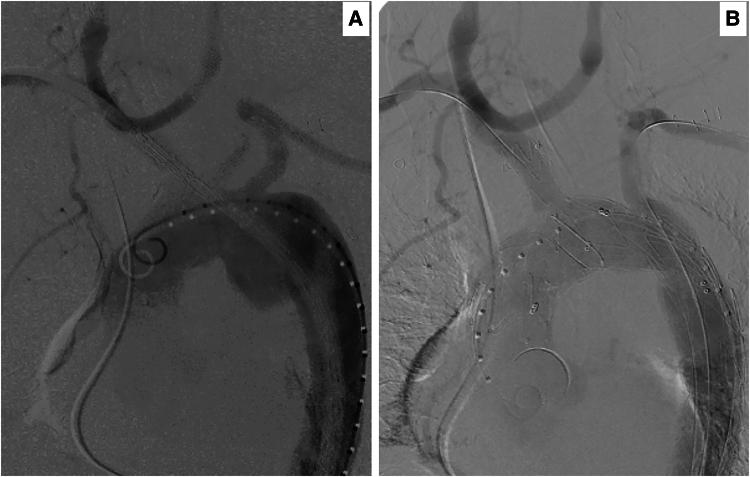

We present a 66-year-old male initially referred with a 7.35 cm giant thoracic aortic arch diverticulum (TAD). It was initially discovered incidentally as a 2.1 cm type 3 Salomonowitz; however, it subsequently increased to 7.36 cm following the third COVID-19 infection with cytokine storm. He underwent a right-to-left carotid necklace C-shaped configuration cross-over bypass using an 8 mm ringed Dacron silver graft. Six weeks post-bypass, the patient underwent a successful repair of TAD using the NEXUS-Endospan-Artivion system (Artivion™, GA 30144, USA), employing a double inner branch to the innominate and left subclavian artery through a single groin approach. Postoperatively, he recovered fully without any neurological or cardiovascular issues with no signs of endoleaks, graft migration, or separation.

我们报告一名66岁男性,最初因一个7.35厘米的巨大胸主动脉弓憩室(TAD)前来就诊。它最初偶然被发现为一个2.1厘米的3型萨洛莫诺维茨憩室;然而,在第三次感染新冠病毒并出现细胞因子风暴后,它随后增大到了7.36厘米。他接受了使用8毫米带环涤纶银移植物的右向左颈动脉链C形交叉旁路手术。旁路手术后六周,患者使用NEXUS - Endospan - Artivion系统(美国Artivion™,GA 30144)通过单腹股沟入路对无名动脉和左锁骨下动脉采用双内分支成功修复了TAD。术后,他完全康复,没有任何神经或心血管问题,也没有内漏、移植物移位或分离的迹象。